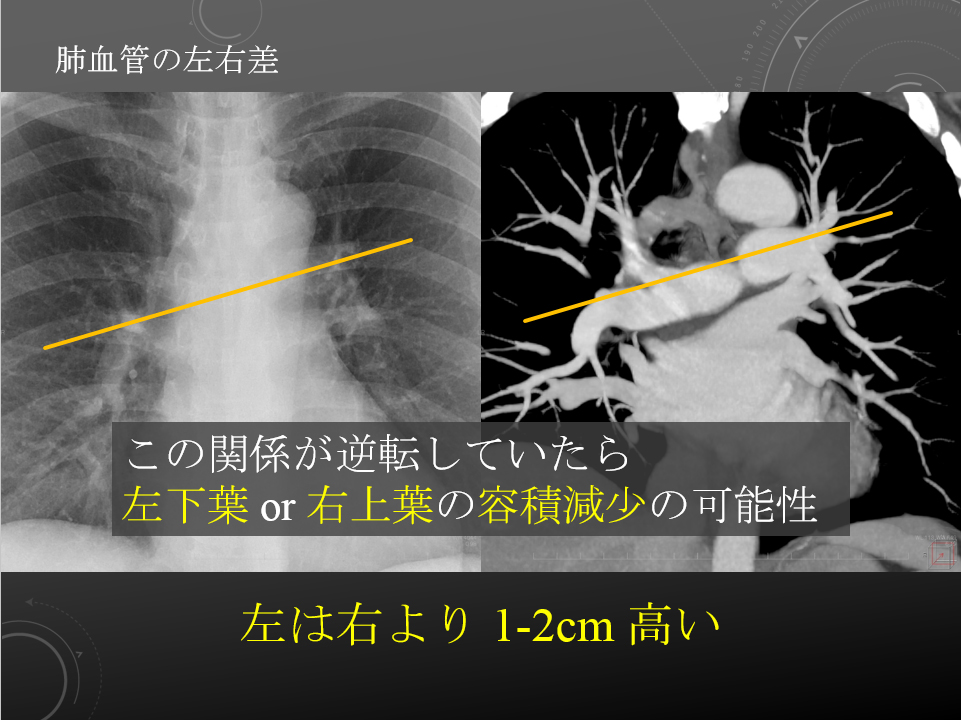

右肺動脈は中間気管支幹の前を横切りながら右下肺野に向かう。

左肺動脈は左主気管支内側を前から後ろに乗りこえ、下方に走行する。

左は右より 1-2cm 高い。

右肺動脈は中間気管支幹の前を横切りながら右下肺野に向かう。

左肺動脈は左主気管支内側を前から後ろに乗りこえ、下方に走行する。

左は右より 1-2cm 高い。